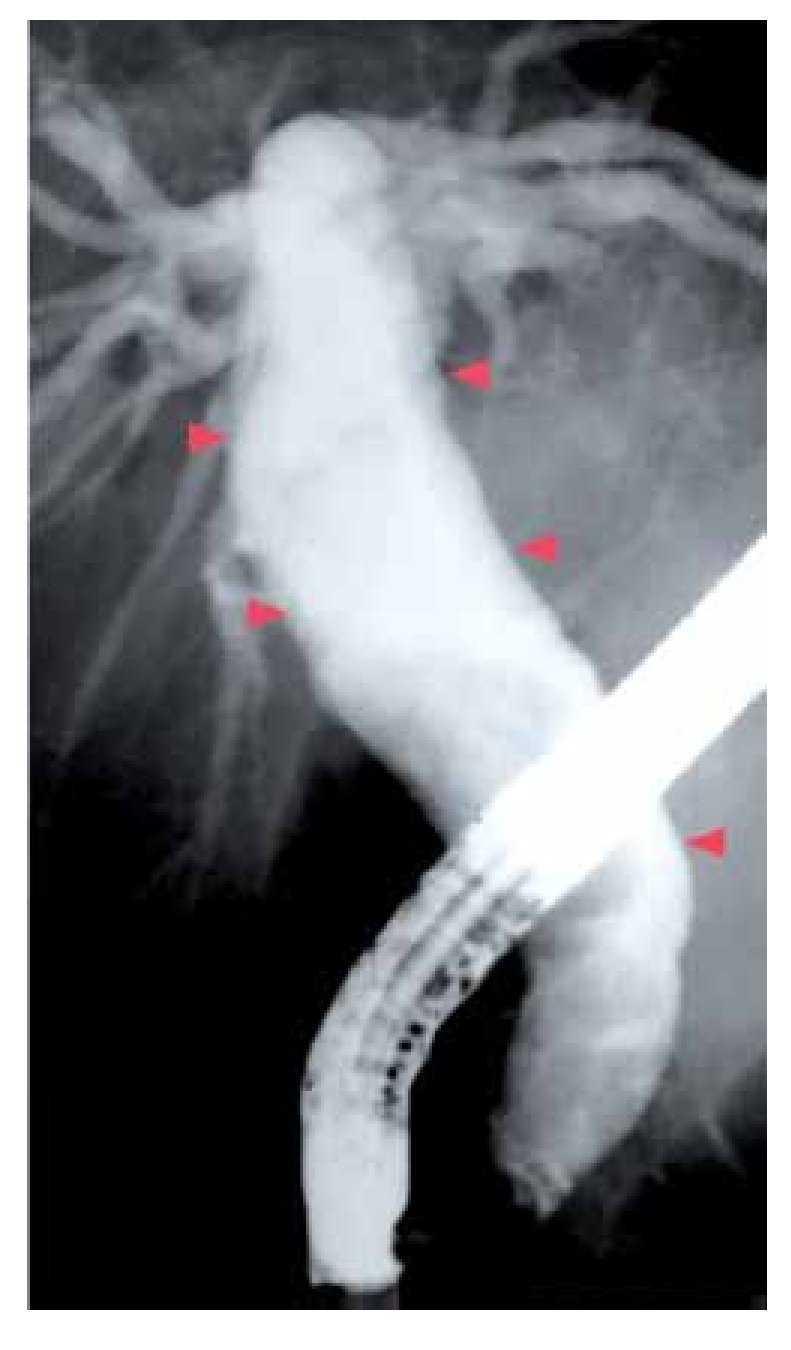

¿ Figura 4. Variantes anatómicas del conducto colédoco. a) quiste de colédoco con dilatación fusiforme del colédoco localizada debajo de la confluencia de los conductos hepáticos derecho e izquierdo.

a. Quistes del colédoco, cuya presentación más frecuente es la dilatación quística fusiforme del colédoco (Figura 5), localizada debajo de la confluencia de los conductos hepáticos derecho e izquierdo.9

¿ Figura 6. Colangiografía que muestra quiste de colédoco (dilatación fusiforme). La imagen muestra un quiste de colédoco tipo I de la clasificación de Todani. La dilatación fusiforme del colédoco (puntas de flecha) se localiza debajo de la confluencia de los conductos hepáticos derecho e izquierdo.